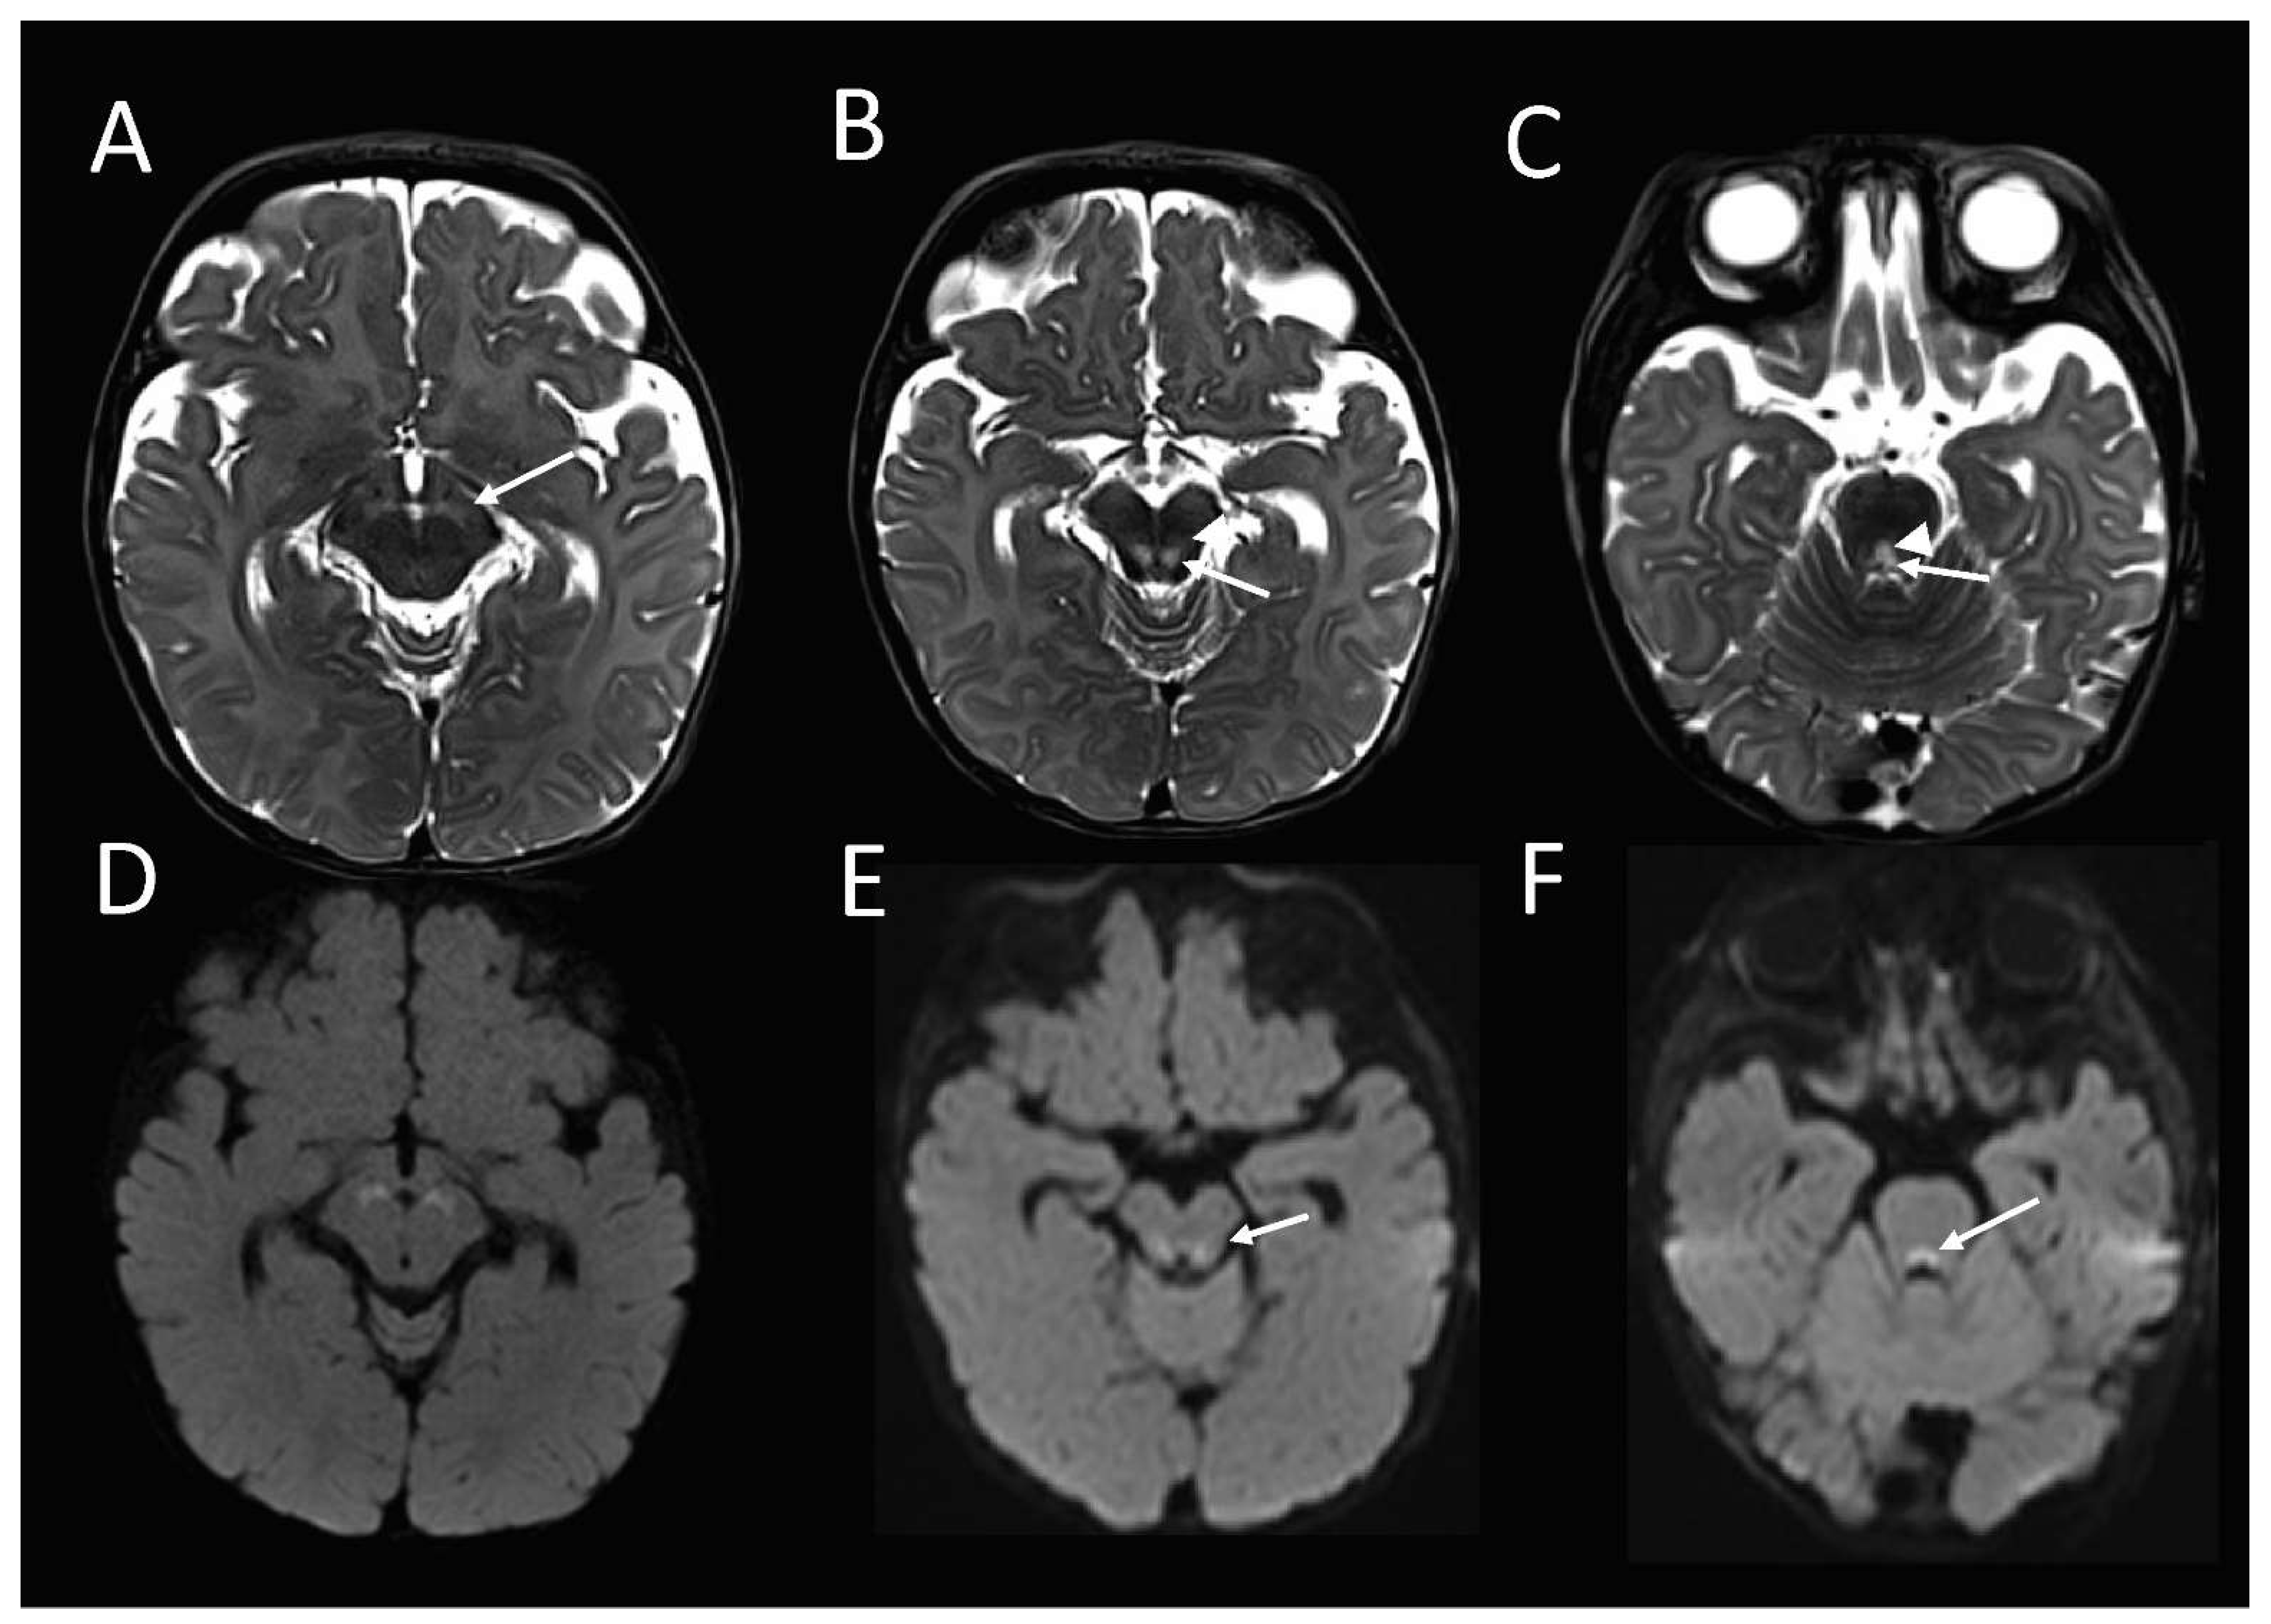

The brain MRI at 16 weeks of age demonstrated an abnormal high T2-weighted signal in the substantia nigra (Figure 1A), bilateral symmetric foci in the midbrain tegmentum, corresponding with the central tegmental tracts (CTT) and the medial lemnisci (ML) (Figure 1B), and the dorsal midline upper pons (Figure 1C), corresponding with the tectospinal tracts (TecSP) and the medial longitudinal fasciculus (MLF). These foci were associated with the restricted diffusion on diffusion-weighted imaging (Figure 1D–F), in keeping with the cytotoxic oedema. Spectroscopy that was performed at short follow-up 3 days later, was normal.

Figure 1. Brain MRI from the patient with compound heterozygous PYROXD2 variants at 4 ½ months. The axial T2-weighted sequence shows abnormally high signal in the (A) substantia nigra; (B) midbrain tegmentum, involving the central tegmental tracts (arrow), and the medial lemnisci (arrowhead) and; (C) upper dorsal pontine tegmentum, involving the tectospinal tracts (arrowhead) and middle longitudinal fasciculi (arrow), with corresponding restricted diffusion (DF) on diffusion-weighted imaging.